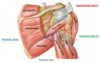

Borders and contents of quadrangular space

- Borders: humerus, triceps long head, teres minor, teres major

- Contents: Axillary nerve and posterior humeral circumflex artery

Borders and contents of triangular interval

- borders: humerus, triceps long head, teres major

- contents: radial nerve profunda brachii artery

Borders and contents of triangular space

- borders: teres minor, teres major, long head of tricpes (lateral)

- contents: scapular circumflex artery